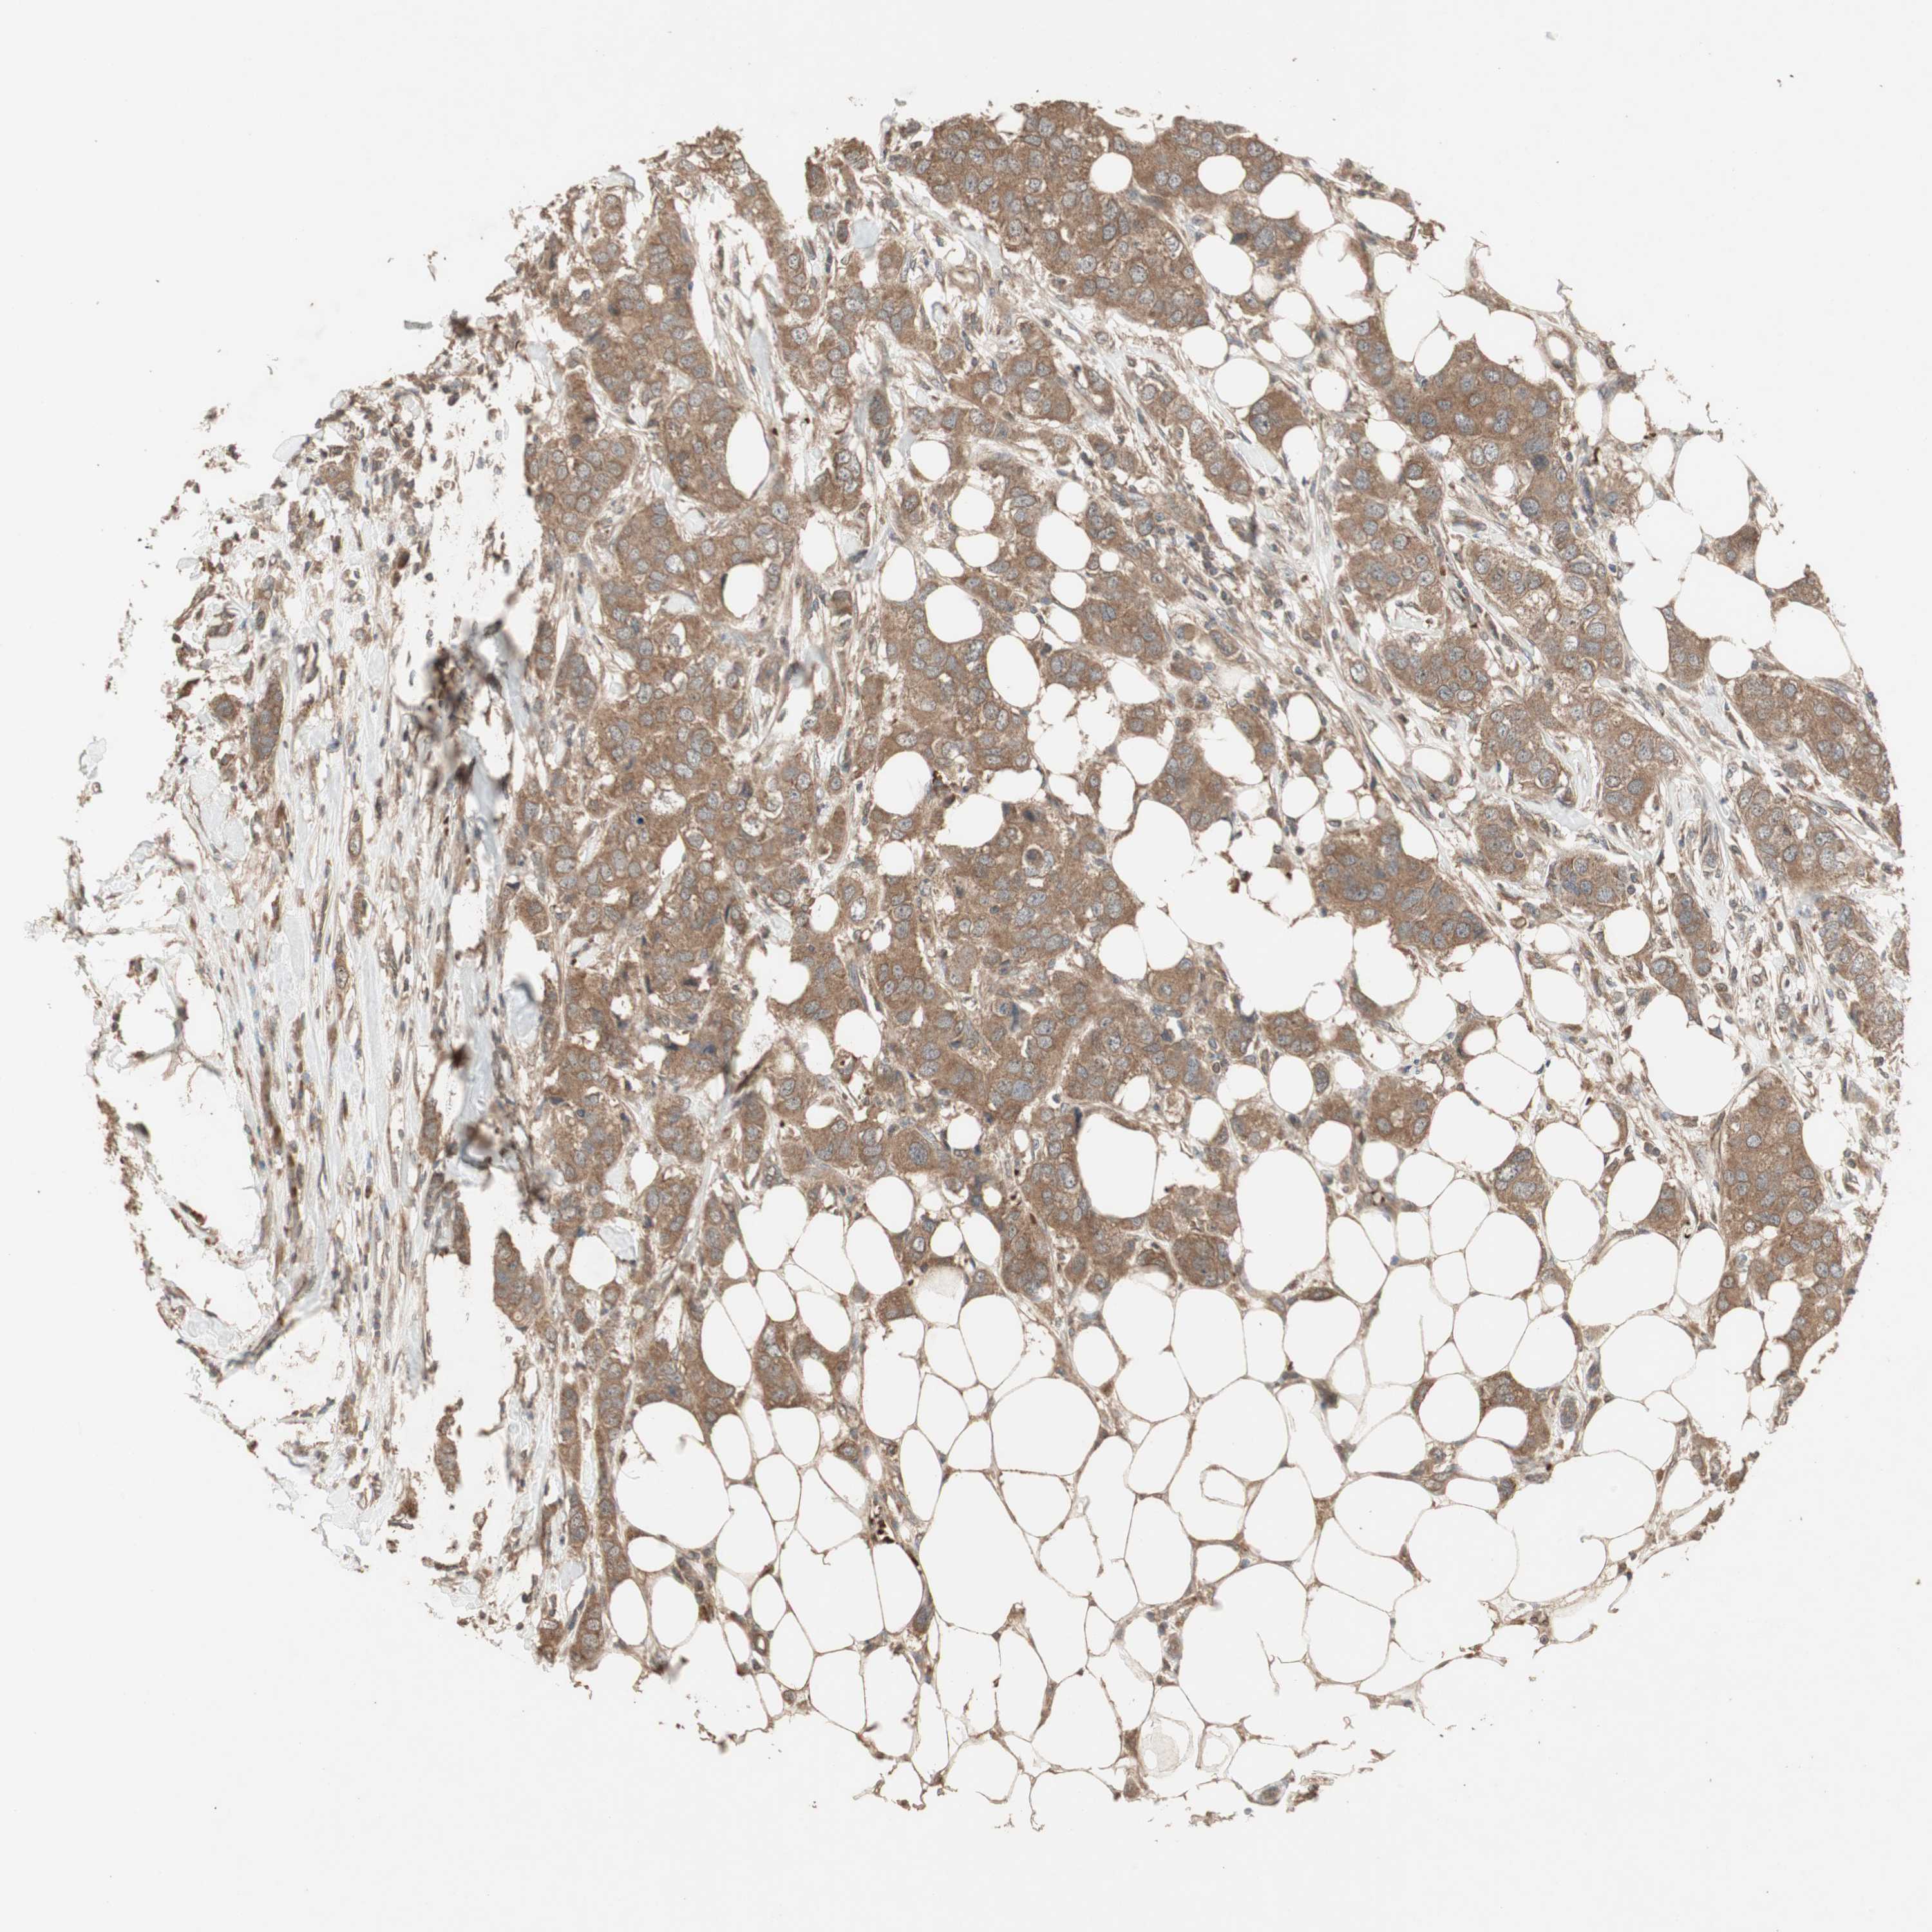

BRCA TCGA BRCA VALIDATION PROTEIN EXPRESSION